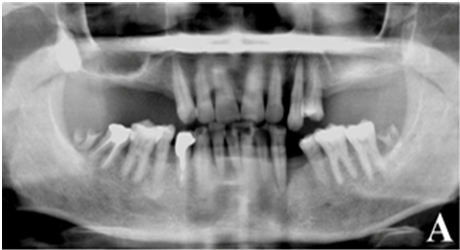

Figure 2a. Initial panorex

ure 2b. Initial Photo with surgical guideFig